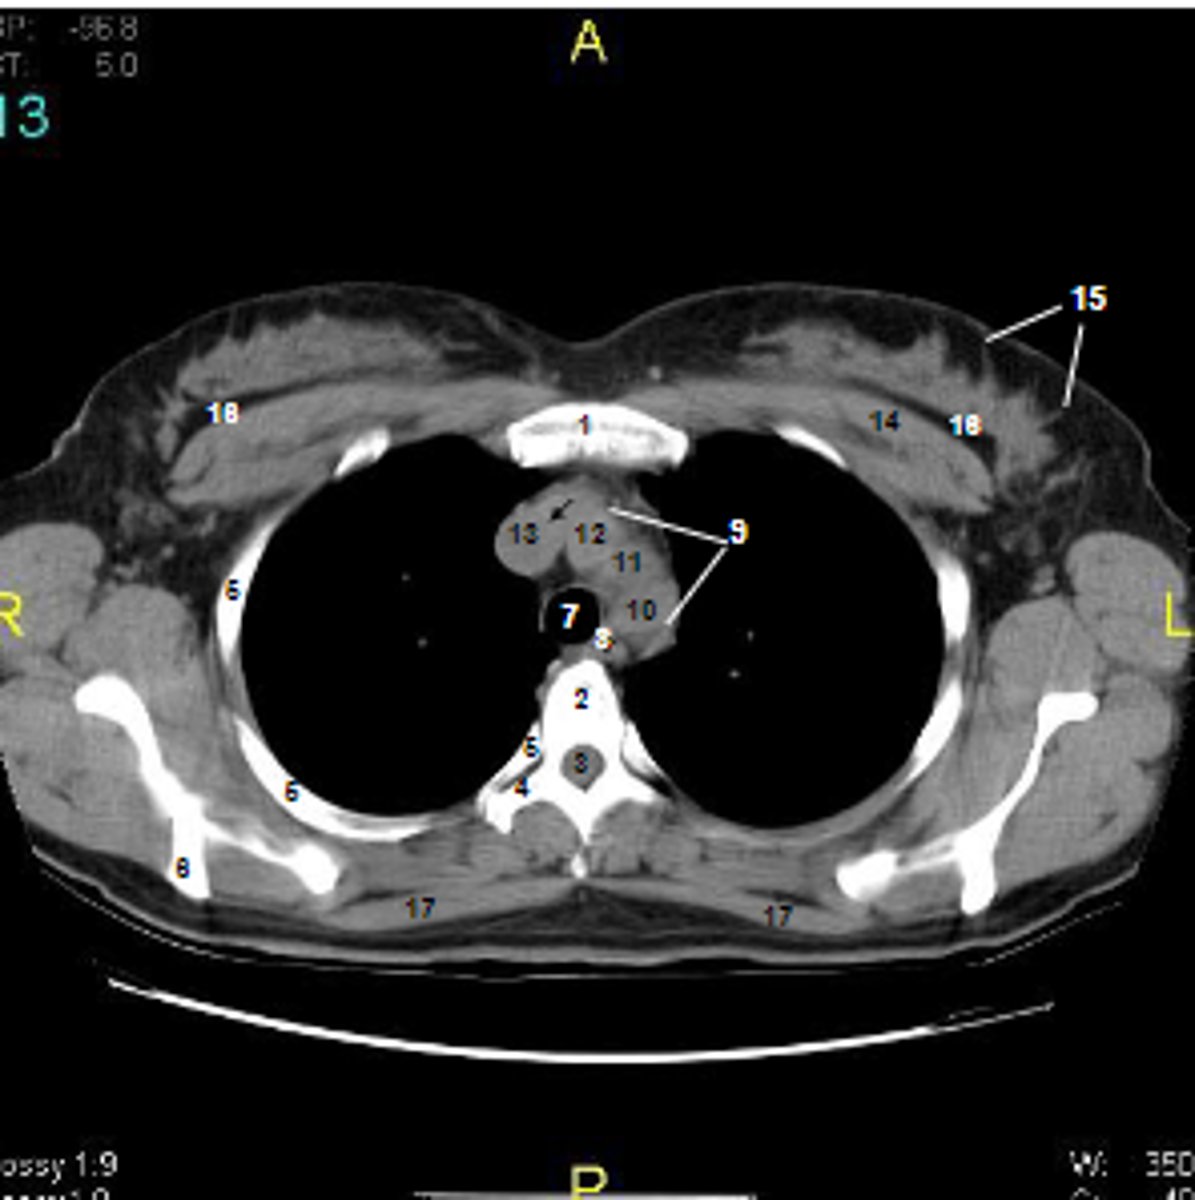

1

at what number is the sternum

2

at what number is the vertebral body

3

at what number is the vertebral canal/ spinal cord

4

at what number is the transverse process of vertebra

5

at what number is the rib

6

at what number is the spine of scapula

7

at what number is the trachea

8

at what number is the esophagus

9

at what number is the arch of aorta

10

at what number is the left subclavian artery

11

at what number is the common carotid artery

12

at what number is the brachiocephalic trunk

13

at what number is the superior vena cava

14

at what number is pectoralis major

15

at what number are Cooper's ligaments

16

at what number is the retromammary space

17

at what number is trapezius